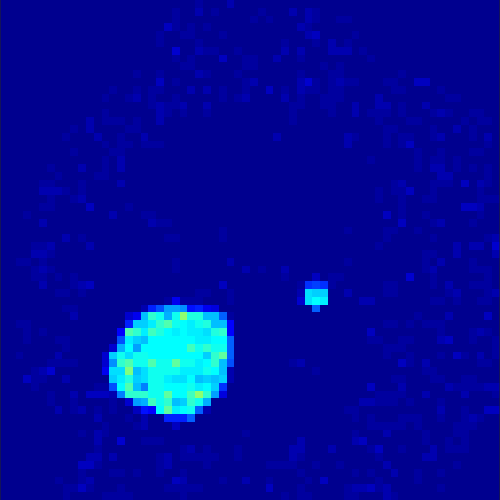

5.2 Monte Carlo Simulation

In order to test the behaviour of the proposed method in a more realistic, random-based test case, we performed a Monte Carlo simulation for dynamic SPECT imaging. First, we created a simple image phantom consisting of an outer and two inner circles which represents the structure of the region of interest (see figure 8(a)). Within those regions we assumed concentration curves over a time period of 90 time steps as displayed in figure 8(b). Based on the tracer intensity in an image frame at each time step, we created a variable number of random decay events (where the number is proportional to the average concentration in one pixel in the whole image frame per time step) with a probability proportional to the concentration in every subregion. They are detected by a virtual double head gamma camera rotating around the patient by 46 degrees per time step, which consists of 374 detector bins. Every simulated decay event is projected onto the scanner and counted by the corresponding detector bin.

In two different tests we fixed the number of events counted by the detector equal to (resp. ) times the average concentration in one pixel. The resulting sinogram images of the accumulated counts in each bin are shown in figure 9.

Based on the sinogram data we applied the proposed algorithm in order to reconstruct the original image sequence. The results for both test cases are shown in figure 10.

As one can see, the method is able to reconstruct the regions properly, even in case of a low count number. Within a number of iterations (average of 100 outer and 10000 inner iterations), the algorithm presents a reasonable reconstruction of the region of interest and the corresponding regional tracer concentration curves. Here, the parameters were not optimized as in the case of the synthesized data sets in the previous section, but kept fixed as , and . With futher optimized parameter values one could possibly provide even better results.